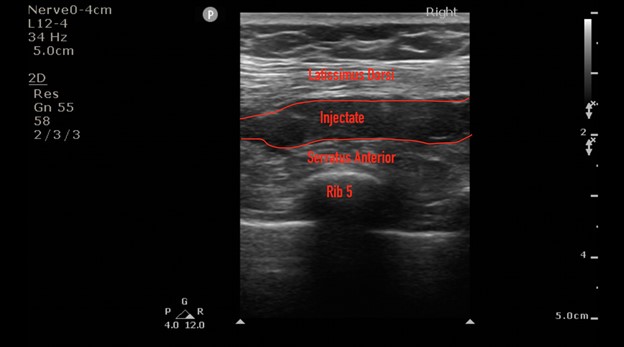

Target directed pain management therapies to the causal nerve, bone, or tendon provide a unique way to provide analgesia while decreasing the need for opiate consumption. The Serratus Anterior Plane Block (SAPB) is a commonly used regional block that was developed as a safer alternative to the thoracic paravertebral and neuro-axial thoracic epidural.3 It provides hemi-thoracic analgesia by blocking the thoracodorsal, long-thoracic, and intercostal nerves from T2-T9. Herein, we describe the use of a SAPB for non-emergent thoracostomy for the treatment of a spontaneous pneumothorax. The patient was a 62 year old male who presented to the ED with worsening dyspnea and was found to have a moderate-sized right-sided spontaneous pneumothorax without midline shift. The decision was made to pursue the placement of a pig-tail catheter and admit for observation. Prior to pig-tail placement, a SAPB was performed to optimize intra-procedure and postoperative pain control. The SAP block was performed by placing a linear transducer in the coronal plane in the mid-axillary line, starting at the clavicle and moving caudal to the fourth rib space, wherein the serratus anterior can be identified superficial to the ribs and deep to the latissimus dorsi. A mixture of 15 mls of Bupivacaine 0.5% and 15 mls of saline for a total volume of 30 cc was injected into the fascial plane located between the serratus anterior and latissimus dorsi. This was well below the toxic dose of 2-2.5mg/kg.4 The patient developed analgesia extending from approximately T2/T3 to T8, and the patient tolerated pigtail catheter placement at the fourth intercostal space. The patient required no additional pain medication after the initial placement and had good pain control after being evaluated two hours and six hours after the block was completed. The chest x-ray is provided below.

Ultrasound images courtesy of Christopher Moore, MD